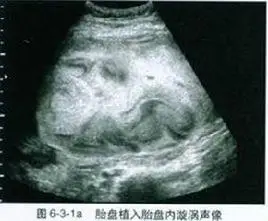

胎盘植入的孕产妇在围产期极易发生致命性大出血.